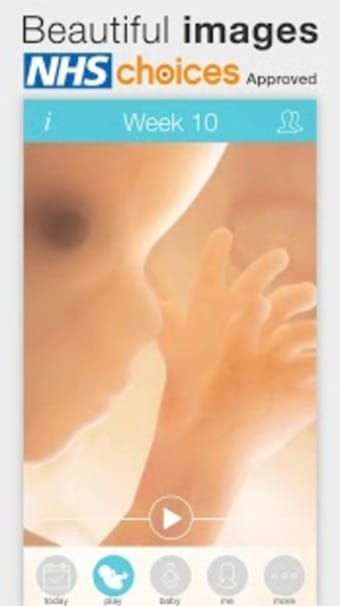

아기의 발달과 진행 상황을 추적하고 손끝에서 올바른 정보를 얻을 수 있는 좋은 방법입니다.

이 앱은 모든 산모가 임신 중에 최고의 경험을 할 수 있어야 한다는 생각으로 만들어졌습니다.